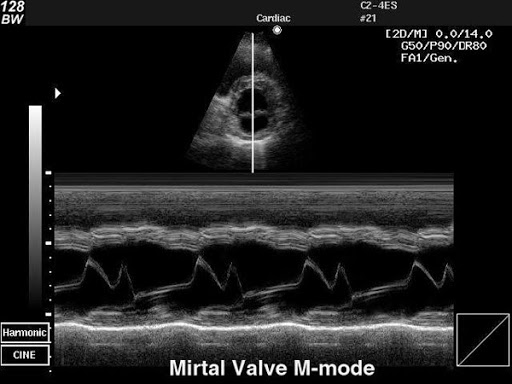

M-mode режим

Метод дает возможность точно оценить скорость и амплитуду перемещения структур сердца за счет высокой временной разрешающей способности.С помощью этого режима можно рассчитать сократительную способность левого и правого желудочков, оценить кинетику их стенок.